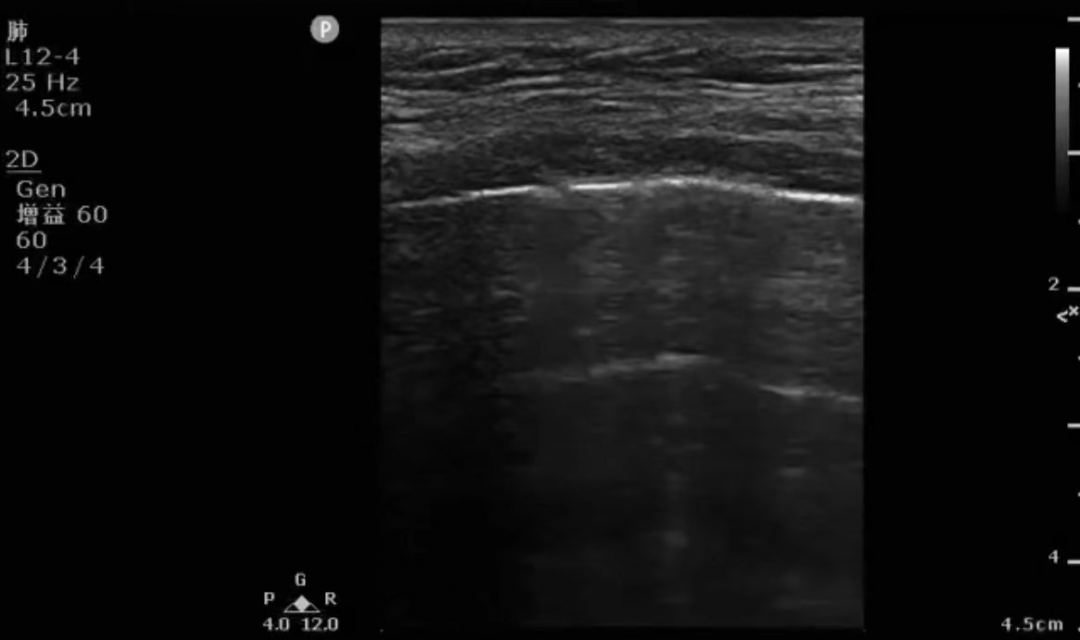

床旁超声是重症医生在接触重症病人时首先使用到的关键设备,因其具有多部位实时动态监测、无创安全、方便快捷的特点,备受重症医生青睐。在急危重患者的治疗和护理工作中发挥着不可忽视的作用,在循环治疗、呼吸治疗、营养支持、容量评估、血管评估、压力性损伤的评估与干预、判断胃残余量及评估膀胱容量等方面得到了广泛的应用,同时在院感防控中也起到了非常重要的作用。

用它我们可以即时评估患者心、肺、肾、胃肠道、颅内等重要脏器功能和血流动力学状态,排除某些危险性疾病(如急性心包填塞、急性心内梗阻、急性肺栓塞、气胸、急性腹腔出血等),进行各种高难度的血管和体腔的穿刺等。在病人病情逐步稳定后,我们可以再次通过超声评估病人治疗后的反应、发现某些潜在的高危因素(如深静脉血栓、肺水肿形成等)。